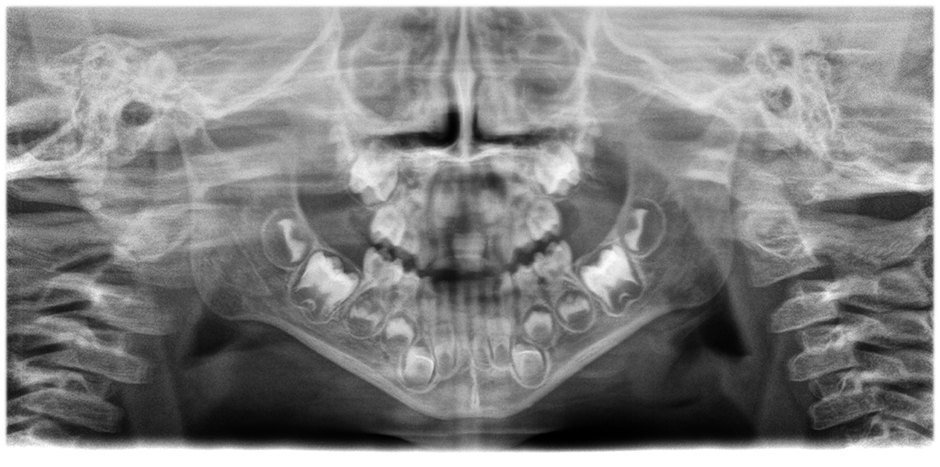

Corrección de posición y movimiento

El avanzado algoritmo de corrección del movimiento lleva la calidad de imagen a un nuevo nivel tanto en imágenes 3D como 2D. Las imágenes 2D mejoran notablemente gracias a un sistema de enfoque automático de 21 capas integrado a la perfección con la corrección de posición.

• Imágenes panorámicas de nitidez y definición extraordinarias

gracias al innovador sistema de enfoque automático de 21 capas integrado a la perfección con la corrección de posición del paciente.

Mueva el botón deslizante para ver la diferencia (a la izquierda, imagen sin enfoque automático; a la derecha, con enfoque automático y posición corregida del paciente).